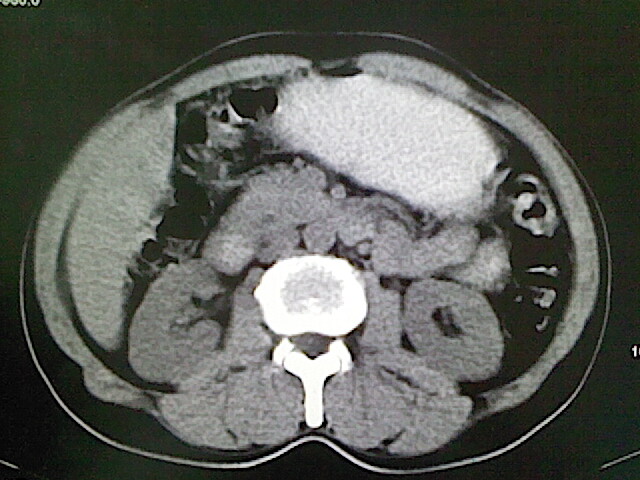

标题: CT18630:男,54岁,乙肝,大家看怎么样? [打印本页]

男,54岁,乙肝,大家看怎么样?

医学影像诊断的基本原则之一是密切结合临床,请你提供简明扼要的病史。

未见明确异常;建议必要时行ct增强扫描检查。

强化再讨论